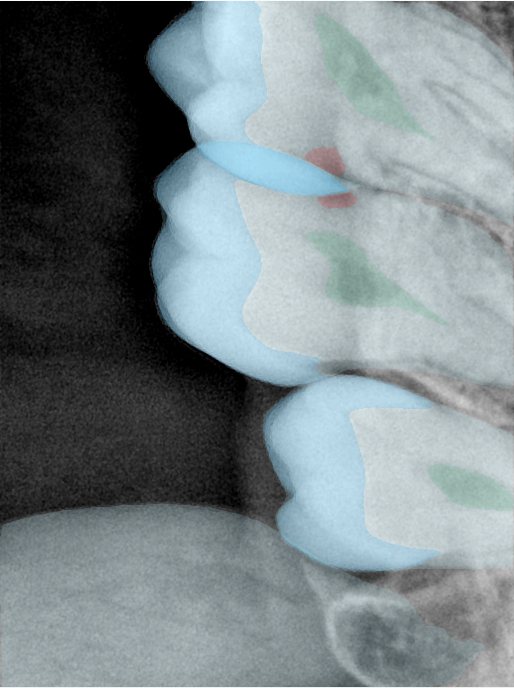

CR/DR 牙齿分割阶段记录

当前进展

- 完成了 CR/DR 牙齿相关分割训练

- 当前结果已经达到阶段预期,但仍有细节问题需要继续处理

相关测试

遇到的问题

- 训练过程中出现过 mask 下移问题

- 部分结果会出现 box 填充异常

- mask 边缘仍然有比较明显的锯齿感